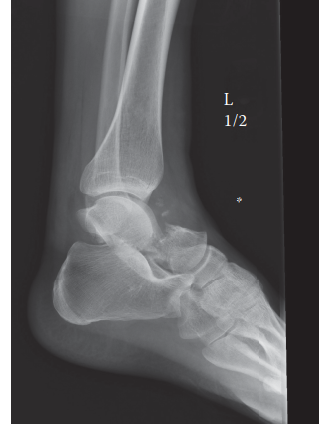

Can you describe the radiograph? This is a lateral radiograph of the left ankle showing a displaced talar nec…